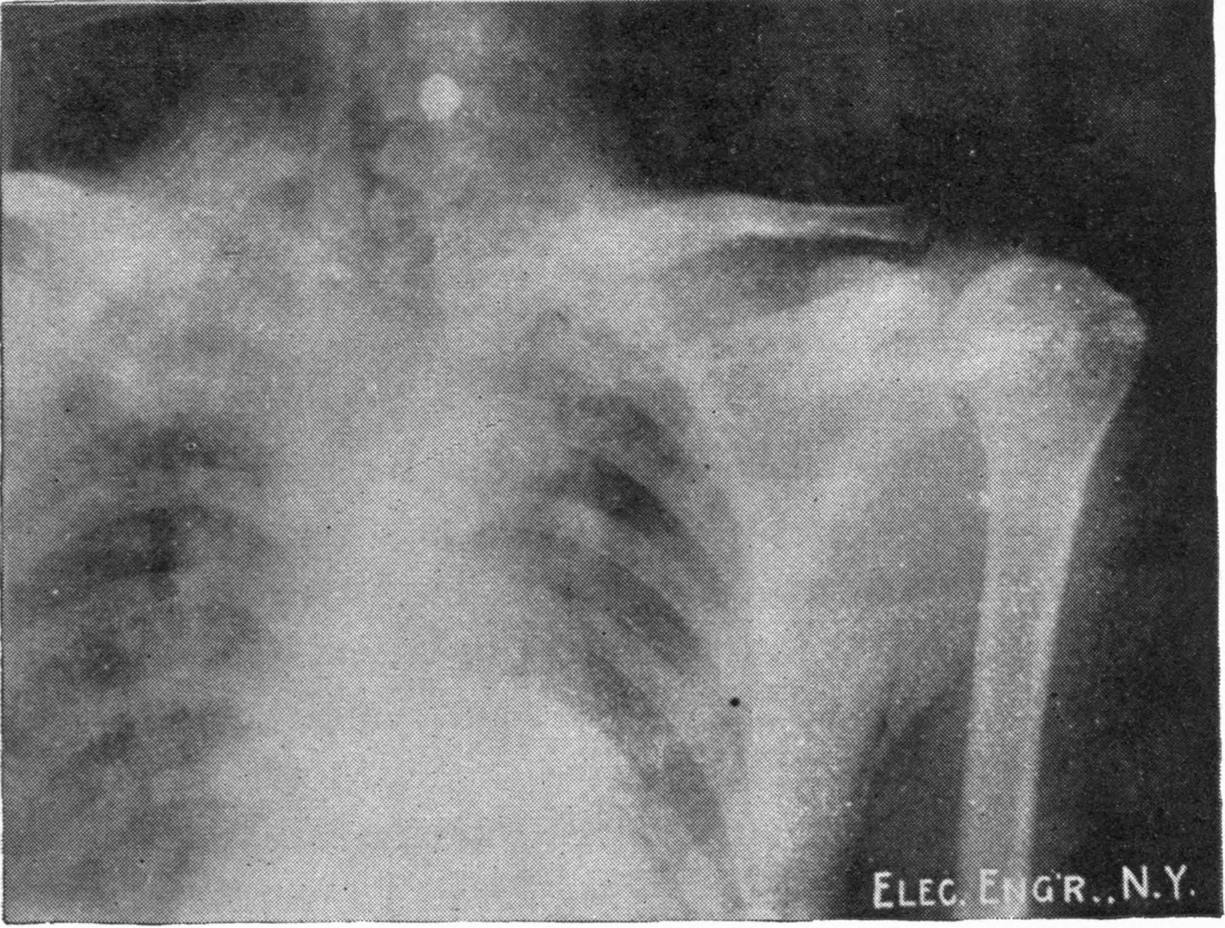

Fig. 1.—Head.

Fig. 2.—Broken Arm, Overlapping.

(Due to defective setting.)

Fig. 3.—Ribs.

Fig. 4.—Knee, Knickerbocker Buttons, Bullet in Femur.

FROM SCIAGRAPHS BY PROF. DAYTON C. MILLER. § 204.